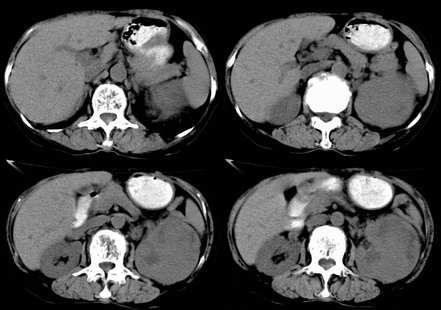

左肾不规则软组织肿块,内见低密度坏死区,与正常肾实质分界不清,左肾明显增大,增强呈不规则条索状强化,肾盂及左输尿管上段扩张。肾周脂肪层受侵、模糊。印象:典型左肾癌。

顺便说几句。肾癌的转移,肾静脉的转移尤为常见,他可以顺沿静脉直至下腔静脉,这种转移,临床中也不少见,笔者遇到过数例。这种转移对于临床来说有较大意义,直接影响手术的成功、手术的方式等,临床有不少肾癌切除术后,静脉残端复发病例。不知楼主有意还是无意,没有给静脉期,或者左肾静脉充盈的图象。

三期抓的不错,典型的肾癌,且已累及肾盂及左输尿管上段

左肾癌累及左输尿管,左肾静脉无受累征象。